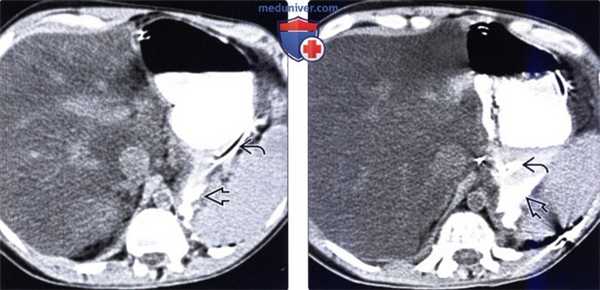

(Слева) На нативной КТ, выполненной мужчине, страдающему алкоголизмом, с жалобами на боль и снижением артериального давления, определяется диффузное уменьшение плотности печени, которое можно объяснить стеатозом либо массивным некрозом печени. Положение назогастрального зонда отмечает заднюю поверхность желудка. Контрастное вещество выходит в малый брюшинный мешок через перфорированную язву.

(Справа) На КТ у этого же пациента визуализируется назогастральный зонд , а также скопление контрастного вещества в малом брюшинном мешке. Во время операции подтвердилась язва, было осуществлено ее ушивание, однако пациент погиб из-за развития острой печеночной недостаточности.